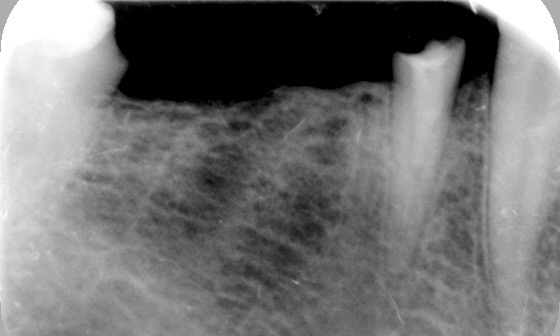

Realizamos previamente una Rx periapical Dígora (radiovisiografía) y un CBCT (TAC de haz de cono) con férula radiológica, marcando ambas raíces del 46 y la raíz del 45.

FIG: 5-6-7-8

Fig. 9

Fig. 10

Fig. 11

Fig. 12